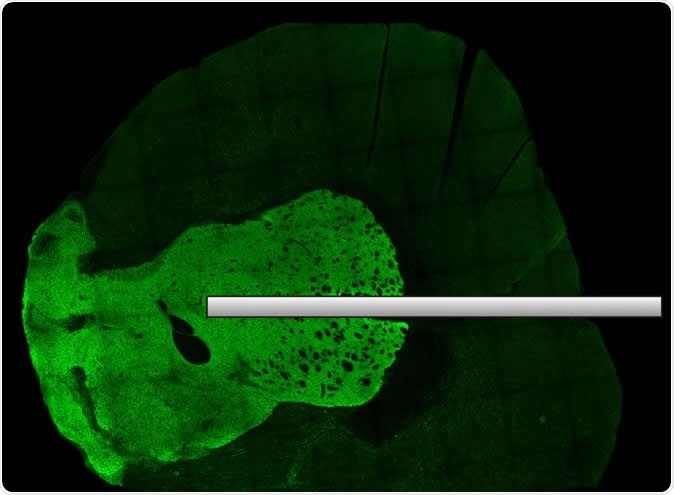

Activity in neuronal tissue can be optically recorded with fiber optics. Image: © 2020 Yagishita et al.